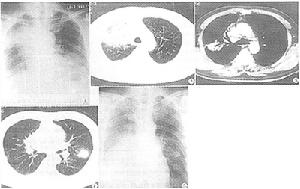

其它輔助檢查: 1.X線檢查 X線胸片所見依病變進展時期而不同典型者表現示兩肺中、下葉有多發性結節狀陰影大小不一,直逕自數毫米至10cm不等,1/3伴有厚壁空洞形成,20%左右僅為單側肺結節陰影。少數表現為肺大片浸潤性陰影1/3可見胸膜腔積液。但肺門淋巴結不腫大。偶爾可見兩肺呈瀰漫性網狀結節性和絨毛狀肺泡浸潤或呈多發性結節性病變,類似於轉移性肺癌病變多為雙側性,主要累及兩下肺野,特別是兩肺外帶結節影可迅速增大或縮小而且甚至可以完全消失。少數患者有縱隔或肺門淋巴結腫大